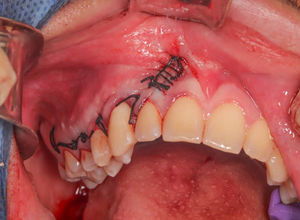

Se reposicionó cuidadosamente el colgajo, para poder realizar la sutura se realizó el bloqueo del nervio palatino mayor y posteriormente utilizando una sutura seda negra 3-0, aguja C24, se realiza el cierre con punto de colchonero vertical de forma interdental, y punto complejo continuo en la descarga realizada en la zona canina. (Fig.10).

Figura 10. Se observan los puntos de sutura realizados, punto de colchonero vertical interdental y punto complejo continuo en la descarga.

Fuente: Historia Clínica Postgrado Cirugía bucal ULAC-IDOLA Julio 2021